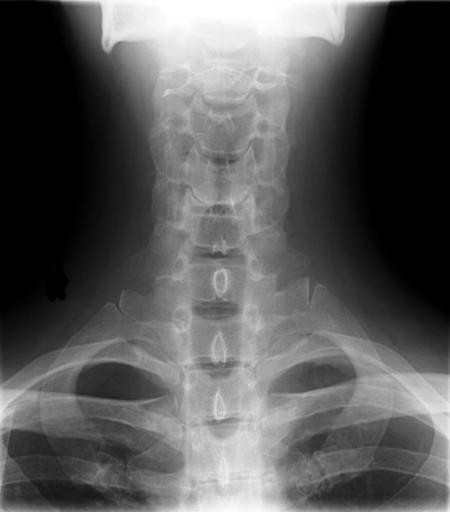

MAKE A MEME View Large Image Cervical Xray Lower AP View.jpg en X-ray of cervical spine neck AP front view This series of x-rays were part of pre-surgical evaluation to help identify spinal instability Patient is a 37 year old male with a history of multiple neck ...

Keywords: Cervical Xray Lower AP View.jpg en X-ray of cervical spine neck AP front view This series of x-rays were part of pre-surgical evaluation to help identify spinal instability Patient is a 37 year old male with a history of multiple neck traumas with pain and muscle spasms and dental implant in lower jaw Excerpt from radiologist's report FINDINGS Five views of the cervical spine including flexion and extension were performed There is no evidence of fracture bone destruction or malalignment There are degenerative bone and is changes at C5-6 There is no evidence of cervical instability on the flexion and extension views The facet joints are well aligned Bony spurring is narrowing the C5-6 neural foramina bilaterally IMPRESSION Degenerative changes at C5-6 No evidence of instability Ragioagraphie aux raysons X du rachis cervical cou AP vue avant Cette série de radiographies faisaient partie de l'évaluation pré-chirurgicale pour aider à identifier une instabilité vertébrale Le patient est un homme de 37 ans ayant des antécédents de traumatismes multiples cou avec des spasmes et des douleurs musculaires et implant dentaire à la mâchoire inférieure Extrait du rapport du radiologiste RÉSULTATS Cinq vues de la partie cervicale de la colonne vertébrale ont été faites dont en flexion et en extension Il n'y a pas de signe de fracture de destruction osseuse ni de défaut d'alignement On observe un phénomène de gégénérescence osseuse des changements en C5-6 Il n'existe aucune preuve de l'instabilité du cou sur les radios montrant la flexion et l'extension Les facettes articulaires sont bien alignés Bony spurring is narrowing the C5-6 neural foramina bilaterally IMPRESSION Changements dégénératifs eu C5-6 Aucune preuve d'instabilité own medical image work for hire Stillwaterising 2010-04 File Cervical Xray Extension jpg File Cervical Xray Extension view jpg File Cervical Xray Lateral View jpg Magnification 0 4x converted from lossy DICOM file Cc-zero Anteroposterior X-rays of the neck Dicom Human anatomy cervical vertebrae